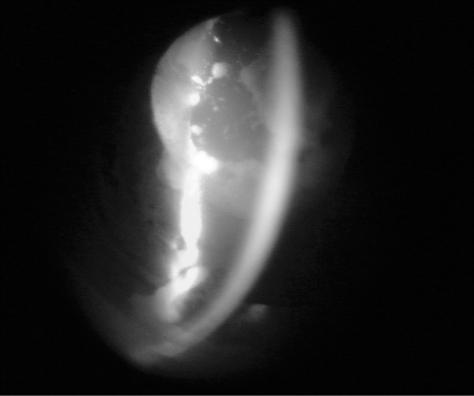

To report acute onset lens particle glaucoma associated with a spontaneous anterior capsular dehiscence. A 66-year-old man presented with spontaneous anterior lens capsule dehiscence with an acute onset of right eye pain that was associated with white particles in the anterior chamber angle and intraocular pressure (IOP) of 55 mmHg. No trauma or other inflammatory antecedents were reported. A hypermature cataract was observed at slit lamp exam. After medical treatment without IOP control, we performed extracapsular cataract extraction and anterior vitrectomy. Anterior chamber aspirate confirmed the presence of macrophages. The postoperative IOP at one month was 16 mmHg OD without medication. Spontaneous dehiscence of the anterior lens capsule in a patient with a hypermature cataract may release lens cortical material, resulting in lens particle glaucoma. Prompt surgical removal of the lens material usually controls the high IOP, and the need for additional glaucoma surgery is not common.